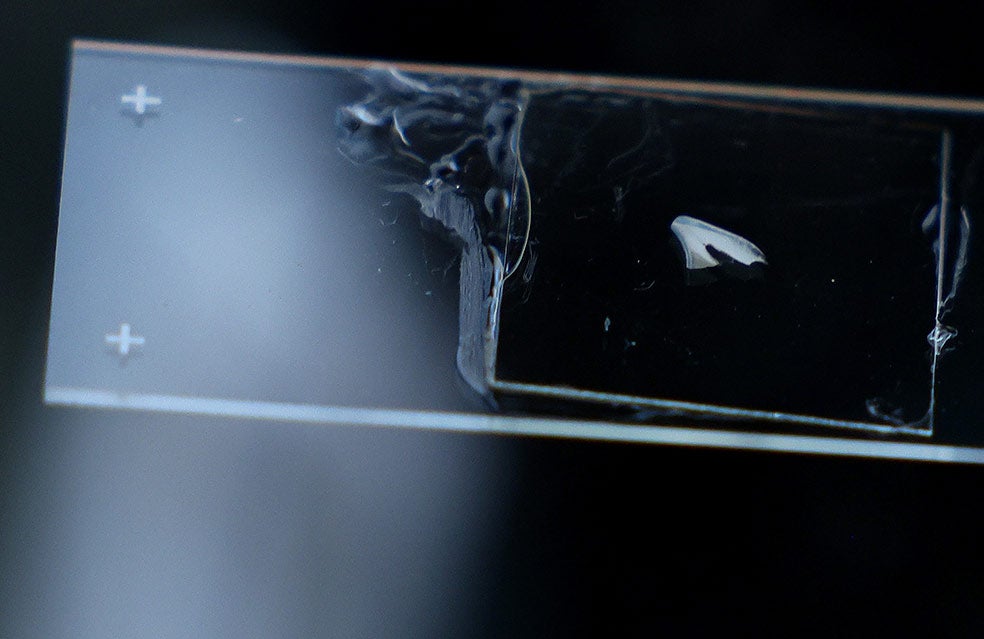

Si la violencia u otro trauma o dificultad (léase guerra o desastre natural) ha aparecido en la infancia, durante el desarrollo de la estructura cerebral, es fácil que los niños crezcan con problemas cognitivos o emocionales o una mayor propensión a padecer cáncer o enfermedades coronarias. Para la investigadora Erin Dunn resulta importante contar con un indicador objetivo que muestre problemas psiquiátricos padecidos en la infancia. Y lo ha encontrado en los dientes que decenas de voluntarios le envían. Son analizados por rayos X y tomografía axial antes de cortarlos en finas 'rebanadas' que permiten analizar los anillos de esmalte. Y buscar huellas de eventos traumáticos.